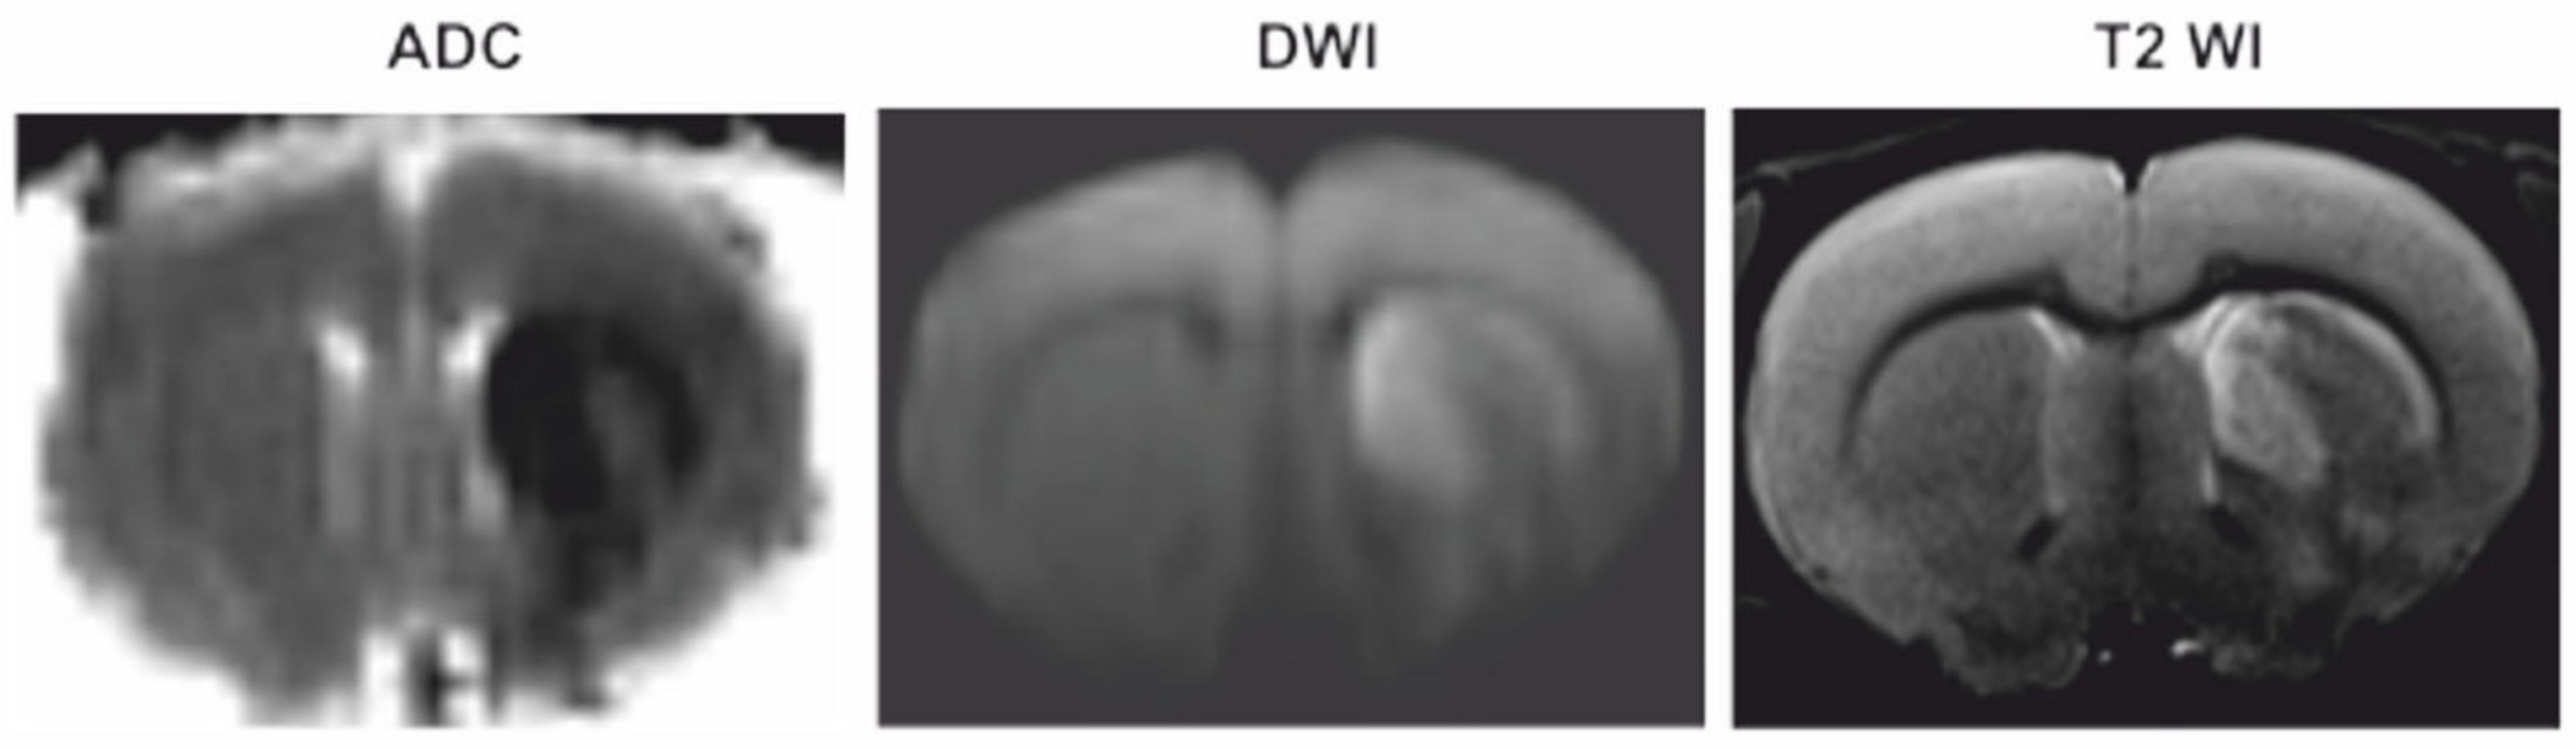

3.1. Magnetic Resonance Imaging (MRI)